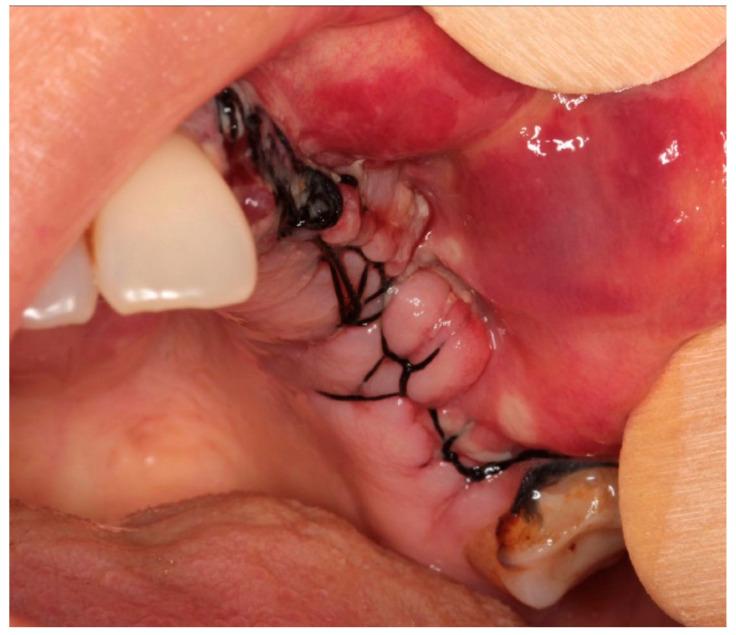

Medication-related osteonecrosis of the jaw (MRONJ) is a drug complication that can occur in patients taking antiresorptive or antiangiogenic drugs. Although it is a well-documented disease, there is no widely accepted treatment. However, several therapeutic approaches have been proposed. The surgical approach in many advanced cases appears inevitable; however, the results are not yet defined and predictable. This study aimed to propose a combined surgical approach with a piezoelectric device and laser (Er:YAG for bone ablation and Nd:YAG laser for photobiomodulation) in a young patient with breast cancer and bone metastasis under denosumab treatment, affected by spontaneous stage 3 MRONJ with maxillary sinus involvement. The patient under study reported no post-operative discomfort, with painkiller intake limited to the day after surgery. Total mucosal healing was observed without recurrences for more than 4 years after surgery. According to the results of our preliminary study, a combined surgical approach using a piezoelectric device and laser therapy is effective in managing patients affected by MRONJ, leveraging the clinical and biological advantages of these different techniques.

药物相关性颌骨坏死(MRONJ)是一种可发生于服用抗吸收或抗血管生成药物患者的药物并发症。尽管它是一种有充分文献记载的疾病,但尚无广泛接受的治疗方法。然而,已经提出了几种治疗方法。在许多晚期病例中,手术方法似乎不可避免;然而,其结果尚未明确且可预测。本研究旨在为一名接受地诺单抗治疗、患有乳腺癌和骨转移、受自发性3期MRONJ累及上颌窦影响的年轻患者,提出一种结合压电装置和激光(用于骨消融的铒:钇铝石榴石激光和用于光生物调节的钕:钇铝石榴石激光)的联合手术方法。研究中的患者术后无不适,止痛药服用仅限于术后当天。术后观察到黏膜完全愈合,4年多无复发。根据我们初步研究的结果,使用压电装置和激光治疗的联合手术方法在治疗受MRONJ影响的患者方面是有效的,利用了这些不同技术的临床和生物学优势。